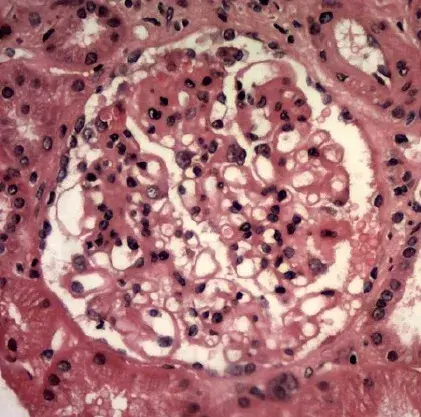

Nefropatia Membranosa: e se o paciente não responder ao tratamento inicial?

Neste vídeo, abordamos estratégias para lidar com pacientes com nefropatia membranosa que não respondem ao tratamento inicial. Ele enfatiza a importância da reavaliação constante e do ajuste do regime de tratamento com base nos resultados e no estado do paciente.

Como fazer o tratamento da Nefropatia Membranosa de forma prática!